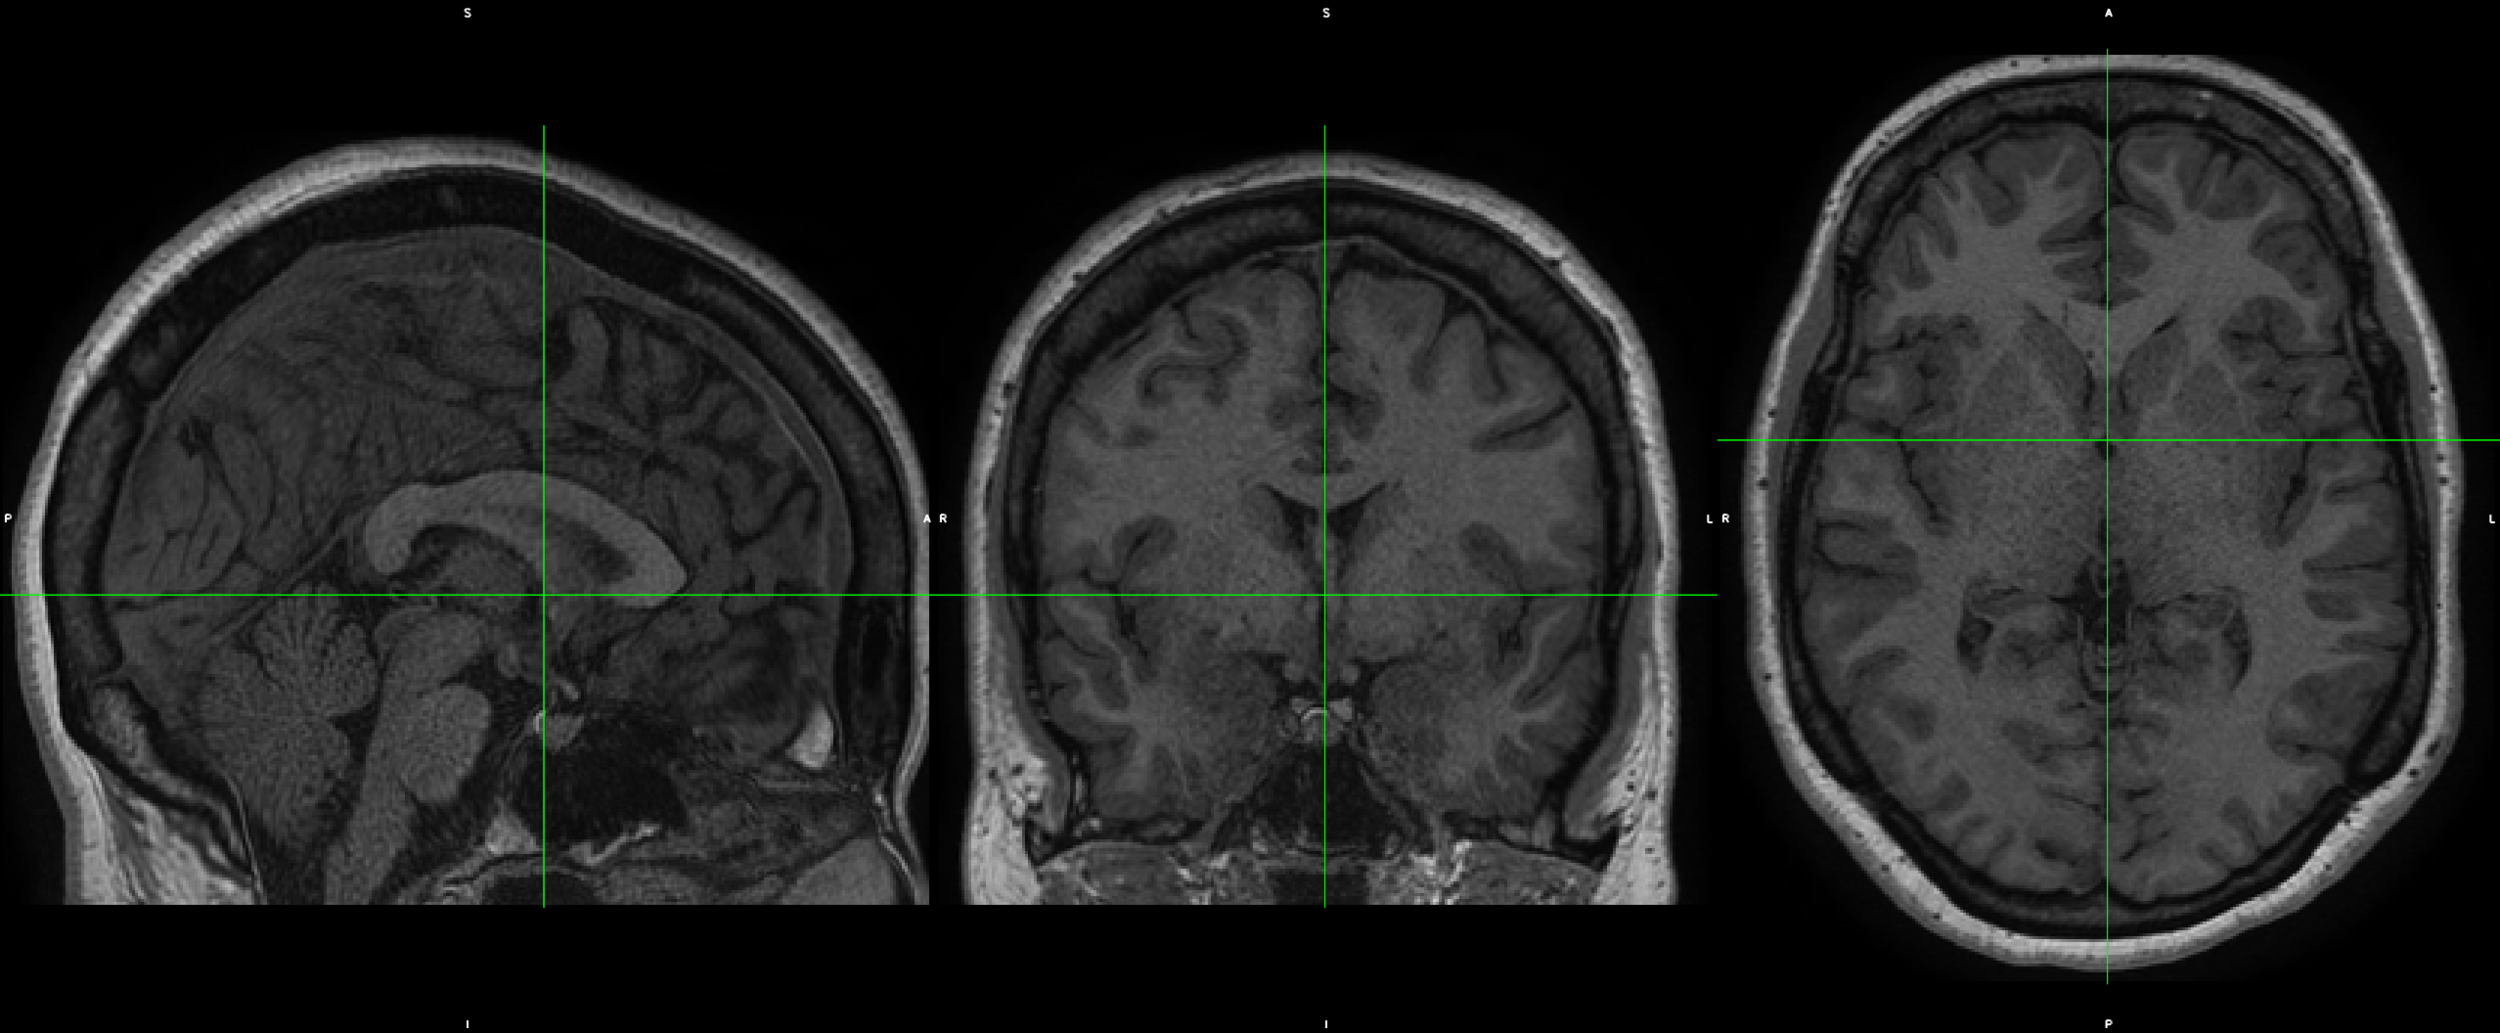

EC2130

T1w_restore

REST1_AP

REST1_PA